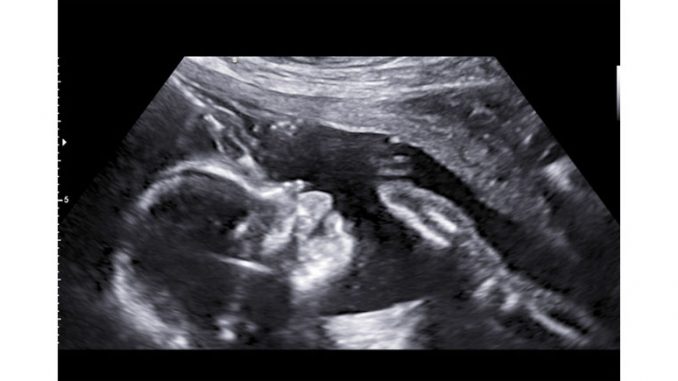

Wenn deine Frau im ersten Trimester ihre Schwierigkeiten mit Übelkeit, Erbrechen, häufigen Toilettengängen und ähnlichen Beschwerden hat, so wird in der 13. oder 14. Schwangerschaftswoche endlich Besserung eingeläutet. Dem Baby geht es in der Regel gut, denn es kann sich nun voll und ganz auf das eigene Wachstum konzentrieren und Fähigkeiten, wie Greifen, Saugen und Strampeln trainieren. Auf dem Ultraschall lässt sich nun sogar die Mimik des kleinen Erdenbürgers erkennen.

In der 14. SSW ist dein Baby im Durchschnitt um die acht Zentimeter groß und wiegt circa 30 Gramm. Das Herz schlägt doppelt so schnell wie das Herz deiner Frau. Dein Baby ist ansonsten damit beschäftigt, die Energie ins Wachstum zu stecken und zusätzlich

Je nachdem, wie das Baby liegt, ist es für einen Gynäkologen ab der 14. SSW erstmals möglich, in einigen Fällen das Geschlecht des Babys zu bestimmen. Falls ihr das Geschlecht nicht wissen möchtet, solltet ihr den Frauenarzt früh genug darüber in Kenntnis setzen, damit ihm kein Hinweis herausrutscht.